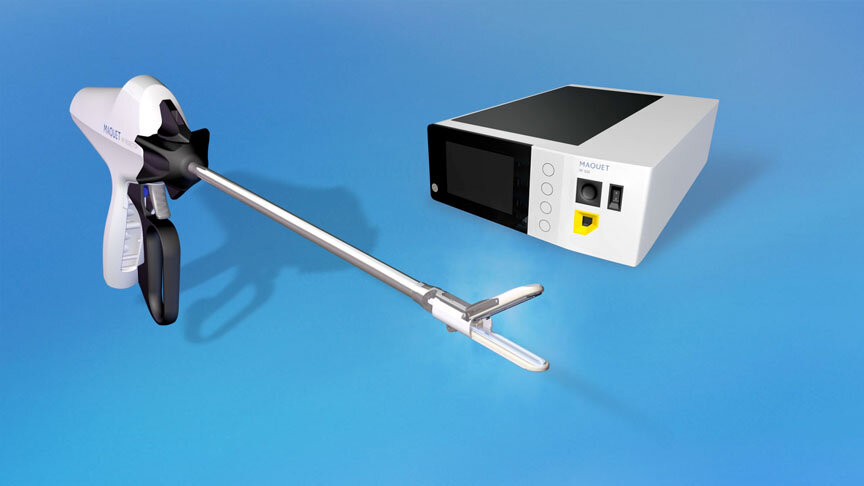

EnCompass F2 Device for cerebral embolic protection system in TAVR procedures

EnCompass Technologies

EnCompass’ F2 filter has pores small enough to block most emboli to the brain while preserving blood flow. During the TAVR procedure, 360-degree wall apposition of the filter in the aortic arch prevents migration. The filter, attached to a self-expanding, nitinol stent, is easy to insert, deploy and retrieve, according to the company. Copyright ©2021 KO Studios.